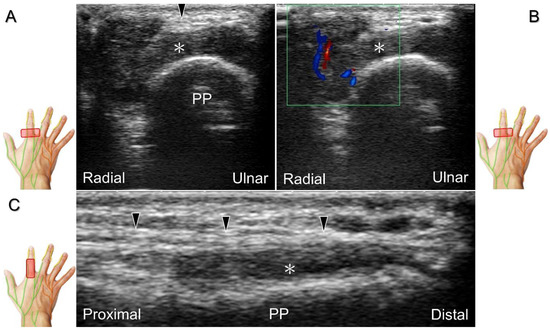

Clinical Implication

Direct injury of the palmar common digital nerve can occur due to various reasons such as trauma, contusion, or iatrogenically during tendon injection. Nerve entrapment caused by space-occupying lesions such as fractures, ganglia (Figure 29A–C), annular ligament tears (Figure 29D), tenosynovitis, foreign bodies, fibroma (Figure 30A,B), or hemangioma (Figure 30C–E) is also likely.

Chronic irritation may lead to the formation of a neuroma, which can occasionally be detected through US imaging (Figure 31). Using the in-plane approach in short-axis view (Figure 32, Video S4), hydrodissection of the entrapped nerves can be performed after identifying the palmar common digital artery and flexor digitorum superficialis/profundus tendons.

Figure 30. In comparison to the healthy side (A), short-axis imaging (B) shows irritation of both the palmar and dorsal proper digital nerves due to a fibroma (asterisk). Short-axis (C) and long-axis (D) imaging demonstrates irritation of the palmar proper digital nerve due to a hemangioma. Spectral Doppler mode (E) confirms the hemangioma. White arrowhead: palmar proper digital nerve; black arrowhead: dorsal proper digital nerve; double asterisk: hemangioma; PP: proximal phalanx.